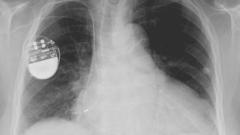

An X-ray, or X-radiation, is a penetrating form of high-energy electromagnetic radiation. Most X-rays have a wavelength ranging from 10 picometers to 10 nanometers, corresponding to frequencies in the range 30 petahertz to 30 exahertz (30×1015 Hz to 30×1018 Hz) and energies in the range 124 eV to 124 keV. X-ray wavelengths are shorter than those of UV rays and typically longer than those of gamma rays. In many languages, X-radiation is referred to as Röntgen radiation, after the German scientist Wilhelm Conrad Röntgen, who discovered it on November 8, 1895. He named it X-radiation to signify an unknown type of radiation. Spellings of X-ray(s) in English include the variants x-ray(s), xray(s), and X ray(s).